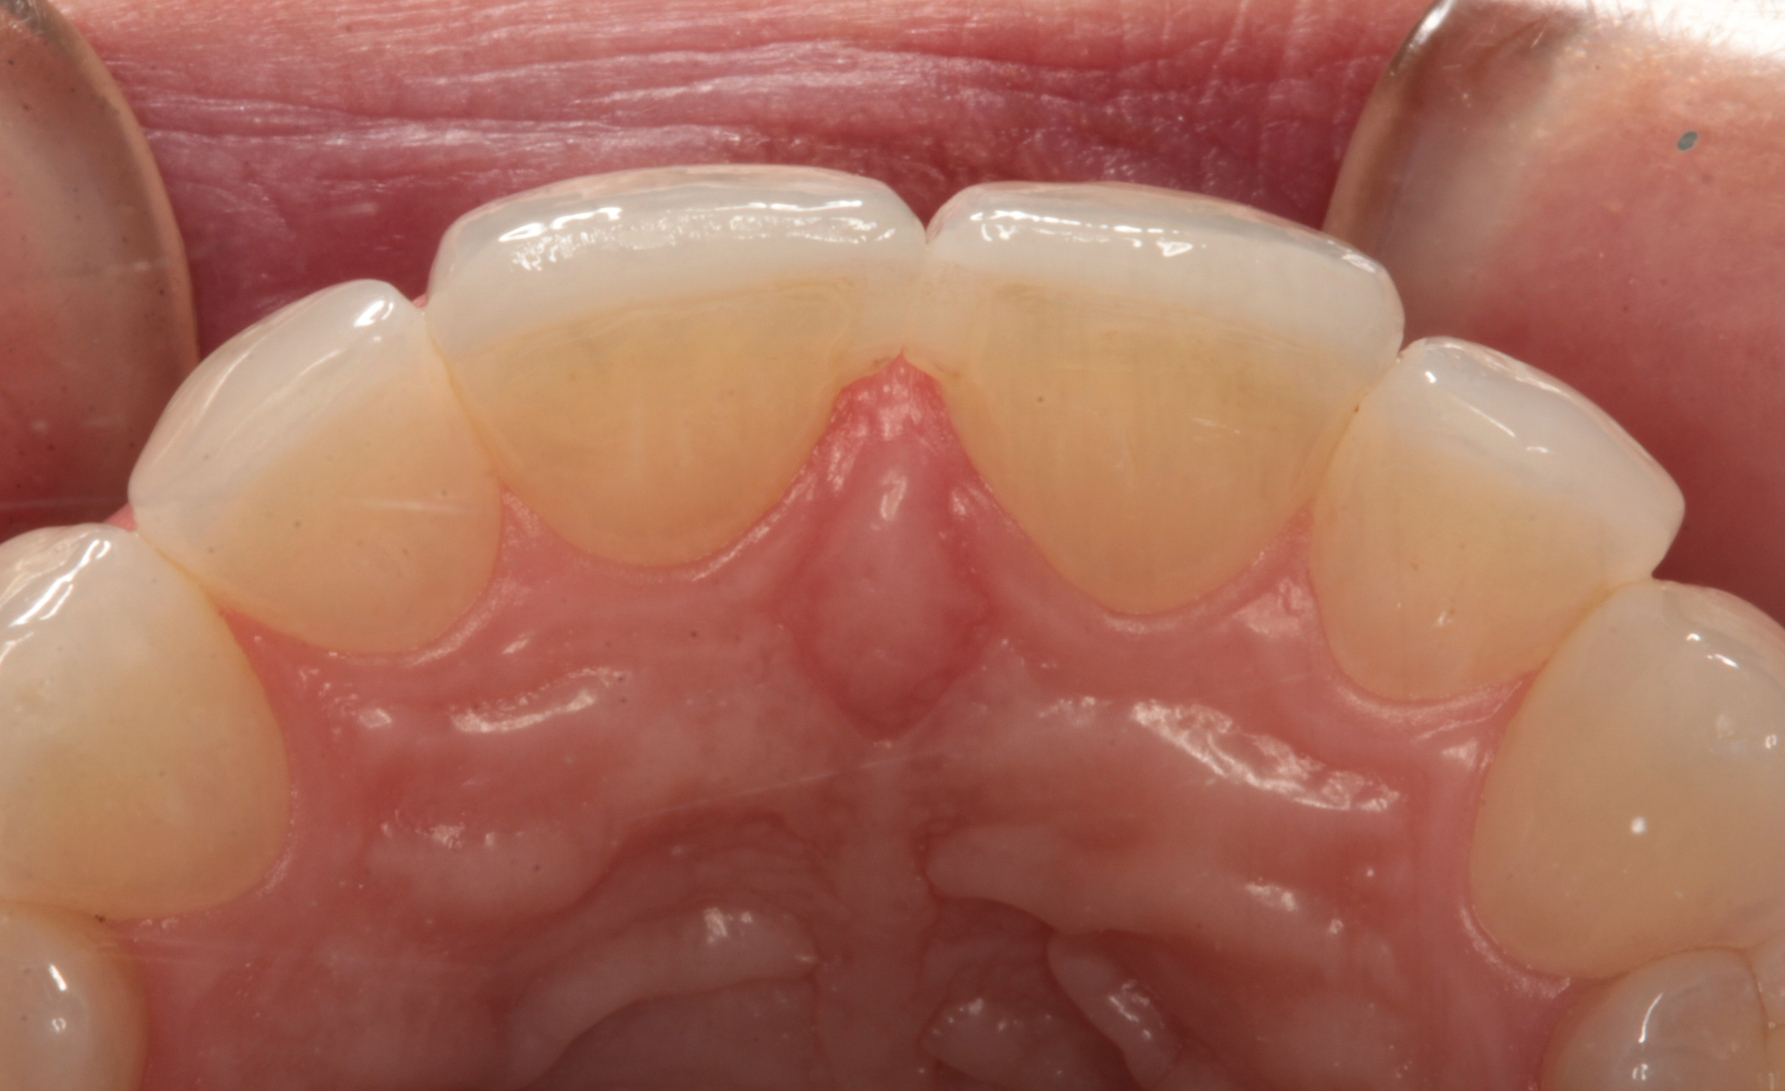

A preoperative impression was taken using Silginat alginate alternative impression material by Kettenbach. The previous laminates were carefully removed using a fine diamond bur (Brasseler) in a high speed handpiece with water spray. The prepared teeth can be seen from the facial view in Figure 4. The incisal view of the prepared teeth is shown in Figure 5. All prepared surfaces were in enamel.

Fig. 4 Fig. 5